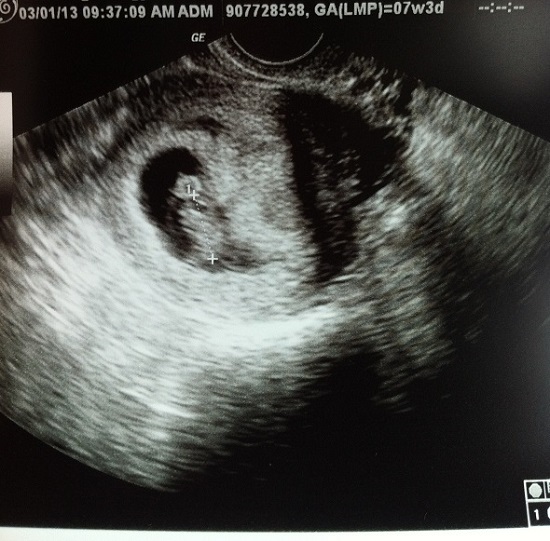

That leads me to the second tied best moment – our first appointment and ultrasound! Seeing that there is something in there is pretty amazing, though it still doesn’t feel quite real – even with all of the symptoms. Maybe when it starts to look like an actual baby. What you’re seeing in this picture appears to be a baby head on top of a lump of a body. Actually, the baby is between the plus signs (crown to rump), and the round thing is actually the yolk sac. The yolk sac will disappear in the next few weeks. I don’t know what yolk sac actually does, but apparently baby eggs have egg yolks too.